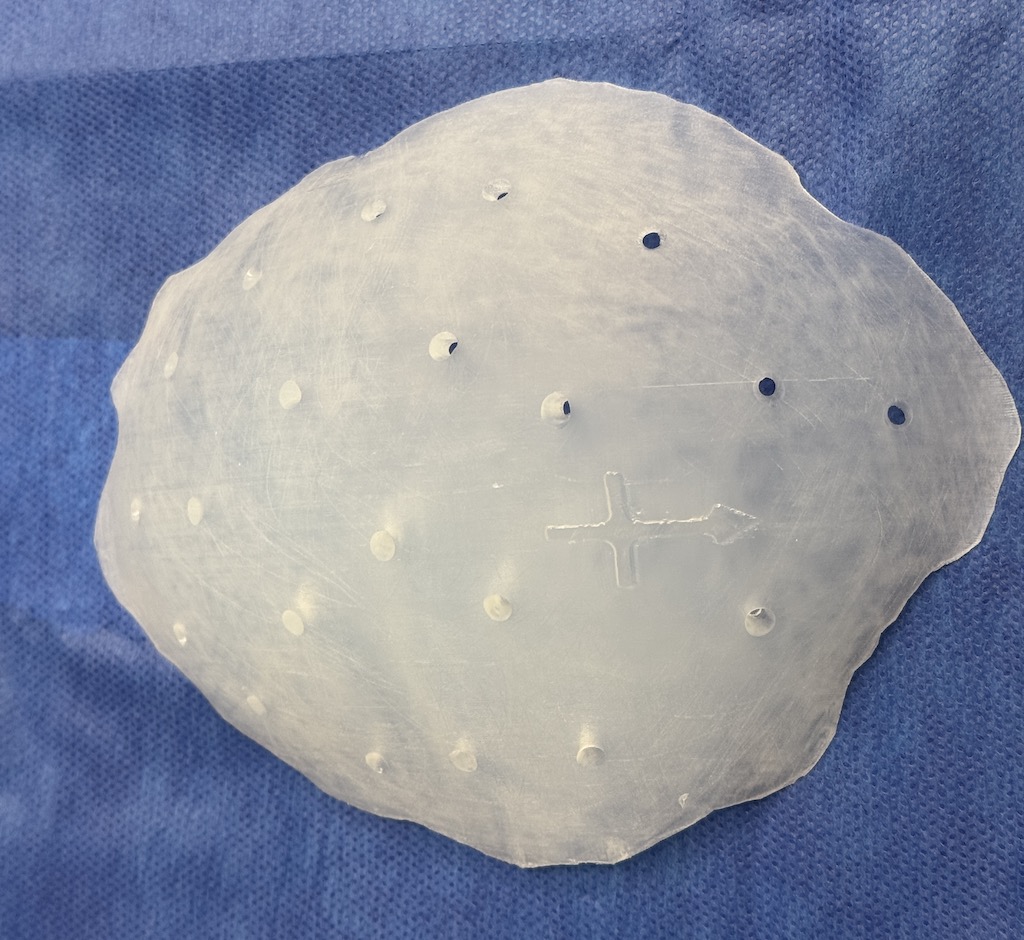

Severe narrowing skull deformity from prior sagittal craniosynostosis repair as an adult.

Complete replacement of entire skull by a custom implant with temporal fat injections.

Severe narrowing skull deformity from prior sagittal craniosynostosis repair as an adult.

Complete replacement of entire skull by a custom implant with temporal fat injections.